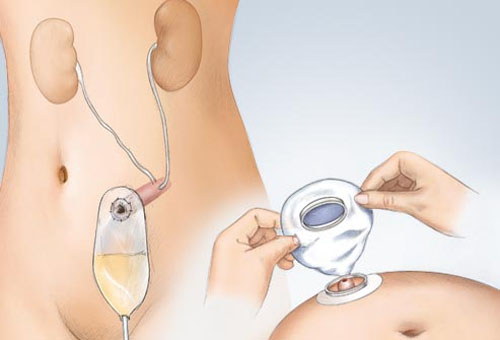

Sau khi cắt bỏ bàng quang, bác sĩ sẽ giúp người bệnh có khả năng đi tiểu bình thường thông qua việc tạo ra một bàng quang nhân tạo.

Sau khi cắt bỏ bàng quang, người bệnh sẽ được tạo bàng quang nhân tạo.